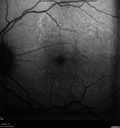

55 year old man: His mother and her siblings have been previously diagnosed with L-ORD - an autosomal dominant dystrophy resulting from a mutation in the c1qtnf5 gene on chromosome 11. The right eye has been abnormal for about the last 1.5 months. When he was trying to read street signs he noticed that his vision was not right. He then covered each eye and noticed that the left eye was normal but the right eye had an area that was blurred with a curve in lines. His right eye with initial vision of 20/32 had a CNVM on FA and responded to monthly Lucentis therapy with restoration of vision to 20/25 after monthly injections. The left eye sees 20/16

Late Onset Retinal Degeneration (L-ORD)506 views55 year old with acute vision loss from a CNVM in the right eye. He responded to Lucentis therapy. His mother and her family has been confirmed genetically to have L-ORD and were part of the early reports.00000